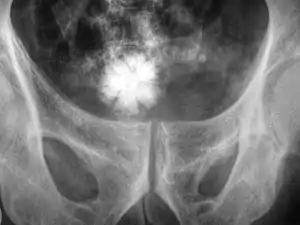

| یک سنگ ستارهای شکل در مثانه | |